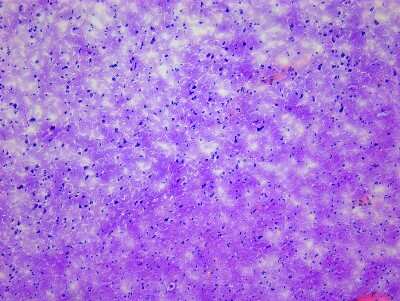

8 results for "Brain Postcentral Gyrus Slides and MicroArrays" in Products

Brain Postcentral Gyrus: Slides and MicroArrays